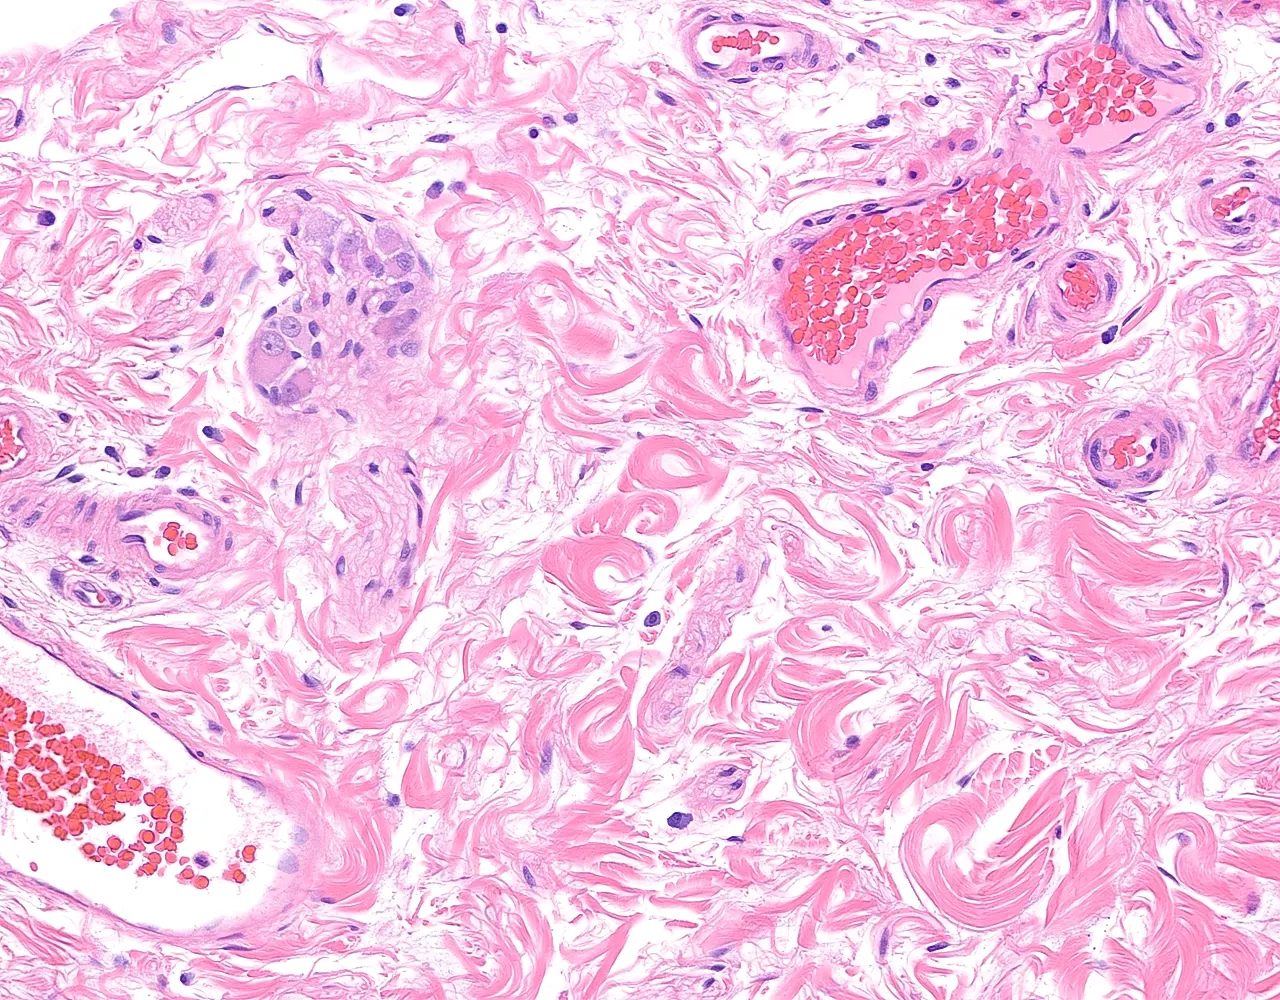

- Le côlon ascendant et le côlon descendant sont majoritairement rétropéritonéaux, alors que le côlon transverse et le côlon sigmoïde sont intrapéritonéaux et recouverts par la séreuse.

- Le rectum est partiellement recouvert par une séreuse dans sa portion proximale, le reste du rectum est entouré par une adventice.